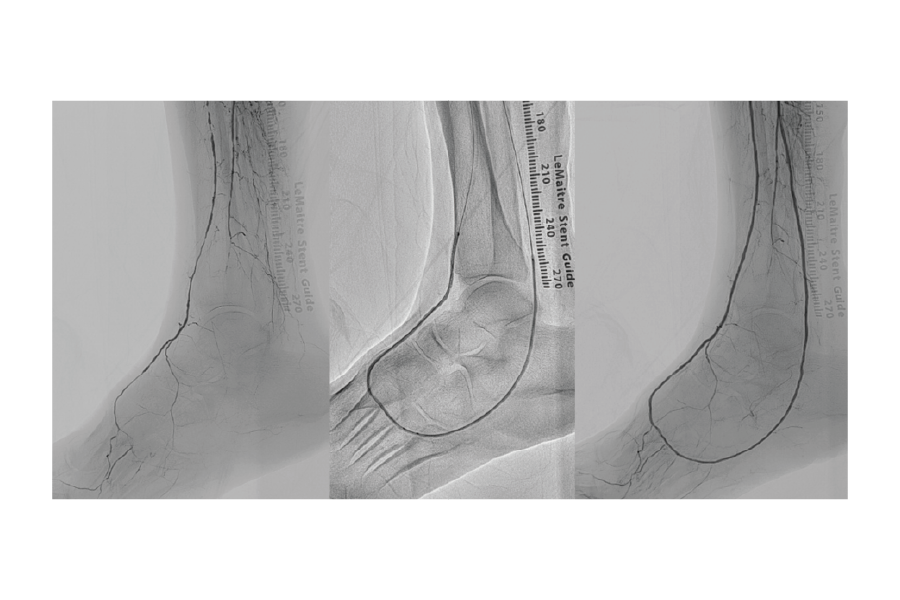

■足の潰瘍

足の指先に潰瘍がある患者様に対して、膝下の動脈の血管内を治療しました。